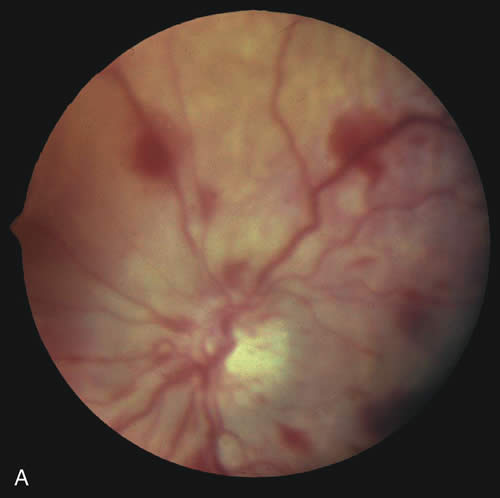

SHAKEN BABY SYNDROME The triad of the SBS includes brain injury usually with hemorrhage, ocular injury, and skeletal injury. These children often have no external signs of trauma. The infant and young child are particularly vulnerable because of their relatively large head, weak cervical musculature, large size of the cranial vault in relation to the size of the brain,3 and immature, unmyelinated brain. Violent shaking causes repetitive anteroposterior and side-to-side disorganized head movement with abrupt acceleration-deceleration forces.7,17,18,19 The magnitude of acceleration-deceleration forces needed to cause brain and eye injuries in humans is extreme but not exactly quantified.20 Although in Caffey's original description, he inferred that normal play activities could cause SBS-like injuries, we now recognize that this is not the case.21 Abusive head trauma is the most common type of child abuse resulting in death,22 although it represents only 3% to 5% of all cases referred to child abuse teams.23 Assault represents more than half of all traumatic brain injury in the first year of life and 90% of brain injuries between 1and 4 years of life. The average age of SBS victim is between 5 and 10 months,22–31 with most children younger than 2 years of age.22,25,26,30 Victims up to 5 years old are rare. The mortality rate of SBS, based on studies with more than 10 patients, is approximately 8% to 61%,23 although this may be a reflection, in part, of separation or imprisonment of perpetrators after the first incident. Recidivism rates are high. The most common perpetrators of SBS are biological fathers and biologically unrelated boyfriends of the mother.22,26,30,32,33 Babysitters, females 4.4 times more often than males,22 are the perpetrators in 4% to 20% of cases.22,26,33 Biological mothers commit this crime in 5% to 12% of cases.22,26,33 Only a minority (10% to 15%)23,33 of perpetrators confess, although it may be as high as 43%34 in fatal cases. SHAKEN BABY SYNDROME: SYSTEMIC MANIFESTATIONS Brain injury in SBS is common: Subdural hemorrhage is found in 10% to 93%, subarachnoid hemorrhage in 10% to 72%, posterior interhemispheric blood in 20% to 100%, stroke in 12% to 50%, intraparenchymal hemorrhage in 5% to 30% and parenchymal tears in 0 to 100%. 23,24,26,29,35 Increased intracranial pressure or cerebral edema is found in 44% to 85%.23,35 The wide variation in incidence figures reflects the nature of the study populations: findings at presentation, in survivors, or at autopsy. At autopsy, subdural hemorrhage, subarachnoid hemorrhage, and cerebral edema are the most consistent findings.21,34,36,37 Although one study using a mechanical model and autopsy investigation suggested that blunt head impact is required to generate the forces necessary to cause the brain injury of SBS,38 a wealth of clinical and pathologic investigations indicate that shaking alone can cause significant injury and even death. Perhaps calculation of forces does not allow for a full understanding as cellular and biochemical responses to shearing stress along with other factors such as anemia and hypoxia may play an important role that cannot be modeled. Violent shaking causes shearing forces that tear the bridging veins running from the cortex to the dural venous sinuses, resulting in subdural and subarachnoid hemorrhage. Shearing also causes diffuse axonal injury with secondary brain edema.39,40,41,42 The diagnosis of brain injury is usually confirmed with computed tomography (CT) scan. However, the CT scan may initially be normal or show edema without hemorrhage. Magnetic resonance imaging (MRI) may be useful to find hemorrhage not visualized on CT43 and to date the findings seen on CT. The long-term prognosis for children with brain injury secondary to SBS is poor. In one study, only 28% of survivors had normal neurologic exams on discharge from the hospital; this figure decreased to 8% to 14% in long-term studies.22 Late findings seen on imaging studies include cerebral atrophy, hydrocephalus ex vacuo, chronic subdural effusion, and encephalomalacia. Patients may have quadriplegia, diplegia, hemiplegia, mental retardation, developmental delay; learning disability, seizures (7% to 65%), and psychiatric/behavioral issues(28% to 50%).23,24,26,30,44 Skull fractures occur in 9% to 31% of shaken babies,23,30 with the parietal and occipital bones most affected. The characteristics of skull fractures that are highly suggestive of abuse include branching, stellate, crossing suture lines, multiple, greater than 5 mm wide, or progressively expanding fractures in a child less than 3 years of age.29 Rib fractures are the most common bone injury in SBS, and are usually posterolateral due to the perpetrator's hands grasping the child. Long bone fractures affect the tibia, forearm bones, femur, or humerus in decreasing order of prevalence. The characteristic metaphyseal fracture, which rarely occurs in young children except in the setting of abuse, results in a “corner” or “bucket handle” chip fracture at the end of the bone (Fig 9). Other injuries seen in SBS include hemorrhagic stripping of the periostium, spiral fractures, and nonsupracondylar humerus fractures—all due to shaking while the infant is held by an extremity, causing the long bones to be twisted and broken.29,30 SHAKEN BABY SYNDROME: OCULAR MANIFESTATATIONS Retinal Hemorrhages Retinal hemorrhage is the most common ocular manifestations of SBS. The incidence of retinal hemorrhages in SBS varies in published reports. This variation is in part due to methods of examination (ophthalmologists vs pediatricians, dilated vs undilated pupils) and the population studied. Overall, the incidence varies from 30% to 100%.18,21,30,38,51,52,53 The incidence in studies including children with abusive head trauma not due to shaking is lower than in studies only involving SBS. In postmortem studies, the incidence of retinal hemorrhages approaches 100%.34,51,54,55 Findings range from a normal fundus to a small number of scattered intraretinal hemorrhages in the posterior pole to massive, confluent hemorrhages from the posterior pole to the ora serrata.(Fig. 10) The hemorrhages may be subretinal, deep intraretinal (dot/blot), nerve fiber layer (flame shaped) or preretinal.19,45 Intraretinal hemorrhages are more common than preretinal or subretinal hemorrhages.32,46 Preretinal hemorrhages must be distinguished from traumatic retinoschisis (see later), which has particular diagnostic significance. White-centered retinal hemorrhages, although classically associated with endocarditis, can occur in any condition that causes retinal hemorrhages, including SBS. Vitreous hemorrhage may be small to massive, and may occur secondary to escape of blood from intraretinal collections or from torn vessels.19 Although vitreous hemorrhage may occur at the time of injury, it may also be a delayed finding occurring 1 to 3 days or more after the initial trauma.47,48 Retinal hemorrhages may be associated with papilledema in SBS. However, papilledema is seen in less than 10% of shaken babies.35, 49 These small, flame-shaped hemorrhages on and radiating around the optic nerve are not necessarily caused by shaking and may be seen in papilledema from any cause. However, retinal hemorrhages associated with SBS may be seen on the optic disc in the absence of papilledema.50 Retinal hemorrhage is usually bilateral but may also be asymmetric or unilateral. Retinal hemorrhage can not be dated with any precision and, therefore, should not be used to help determine when the abusive event occurred.46,47,56,57,58,59 At best, generalizations may be made with wide intervals. For example, intraretinal hemorrhages do not last months, and blood in schisis cavities does not go away in days. Retinal scars or optic atrophy do not form in days. The pathophysiologic mechanisms of retinal hemorrhage in SBS are varied. Vitreous and perhaps orbital shaking is likely to be involved in most of the vitreoretinal injuries. In children, the vitreous is well attached to the retina at the macula, blood vessels, and the periphery. Shaking of an infant causes the vitreous to shake, which, in turn, applies shearing forces to the retina at points of firm attachment. These shearing forces at the macula may split the retina at any layer, causing the formation of a cystic cavity, which may be filled partially or completely with blood (Fig. 11). This traumatic retinoschisis has been well documented in abuse cases by ultrasound, electroretinogram, and pathology.34,58,60,61,62,63,64 Histopathology reveals a widening of the retinal layers or a stripping of the internal limiting membrane. The vitreous may stay adherent or detach. Clinically, to recognize this important finding in SBS, the examiner may observe a hemorrhagic or hypopigmented curvilinear edge to the schisis cavity, with or without a fold in the retina (Figure 11).50,65,66 Recognition of this edge helps distinguish retinoschisis from subhyaloid hemorrhage. However, subhyaloid hemorrhage, which may have originated from blood breaking out of a schisis cavity, may obscure the underlying schisis. It is important to follow any potentially shaken child with preretinal blood in the macula until that blood has cleared as the signs of schisis may be unmasked as the blood resorbs thus confirming the diagnosis of SBS. The retinal fold or hypopigmented line may be a complete circle or just an arc. In the long term, these patients may have surprisingly few sequelae and good vision as the cavity flattens spontaneously. There may also be findings of permanent curvilinear, hypopigmented scars or retinal folds. These provide clues to prior abuse.67

There remain still other theories for retinal hemorrhage in SBS that also seem to play a minor role. Some have suggested a Purtscher-like mechanism due to an increase in intrathoracic pressure when the perpetrator squeezes the child's chest. Although the characteristic white retinal patches of Purtscher retinopathy may be seen in SBS (Fig. 11), there appears to be no correlation with rib fractures,35 and the finding is very uncommon. The failure to see significant retinal hemorrhaging after the chest compressions of cardiopulmonary resuscitation in both animal models and humans also argues against a Purtscher-like mechanism. Differential Diagnosis The differential diagnosis of retinal hemorrhages in a child is vast. However, if one considers a child with the full spectrum of injuries seen in SBS, including brain, skeletal, and eye findings, most would not dispute that the retinal findings are due to nonaccidental injury. However, in a child with a small number of retinal hemorrhages and without retinoschisis, (Fig. 10A) the diagnosis of SBS may be less clear. The birth process is likely the most common cause of retinal hemorrhages in newborns, varying in several reports from 11% to 31% or higher.4,15,78 These retinal hemorrhages are most common after vaginal or vacuum-assisted vaginal delivery.79–82 The exact mechanism is unknown, but there is no association with brain hemorrhages in these infants.79,81,83 Prostaglandin release may play an important role. The distribution of retinal hemorrhages secondary to the birth process may extend from the posterior pole to the ora serrata. Most often they are limited to dot, blot, or flame-type of hemorrhages but preretinal and less commonly subretinal hemorrhage may also be seen.79,81,84 Although macular hemorrhages are common,82,85 schisis has never been observed despite the examination of thousands of children. All types of retinal hemorrhages due to the birth process resolve by 6 weeks of age with the exception perhaps of deep foveal hemorrhage. The majority of hemorrhages clear much earlier. Most flame-shaped hemorrhages resolve by 3 to 5 days, with all resolved by 1 week.86,87 Any retinal hemorrhages seen beyond these dates should arouse suspicion of another cause. Retinal hemorrhages seen within the first 6 weeks of life may also be due to SBS, and additional investigations must be considered when appropriate. Caretakers often relate histories of relatively minor head trauma as the cause of injuries that are otherwise generating the suspicion of SBS.21,34 After much study, most authors88–90 conclude that severe injury after a minor fall should raise the suspicion that the history is false and that the child has been abused. Furthermore, “most investigators agree that trivial forces such as those involving routine play, infant swings, or falls from a low height are insufficient to cause” the injuries seen in SBS.21,91 Even severe accidental head injury such as depressed skull fracture or intracranial hemorrhage does not routinely cause retinal hemorrhages.90,92,93 In compiling the available literature, retinal hemorrhage occurs in less than 3% of accidental head trauma, and then, almost always only in cases of severe, life-threatening injury.35,53,72,91,92,94,95 In the few cases of accidental head trauma with retinal hemorrhage, the bleeding is confined to the posterior pole with dot-blot, flame-shaped, or preretinal hemorrhages. Occasionally, these hemorrhages can extend to the midperiphery. But even the most severe accidental head trauma injuries do not cause the extensive retinal hemorrhages seen in SBS, except perhaps when the injury mechanism involves multiple acceleration-deceleration events such a motor vehicle accident in which the car strikes several objects or rolls consecutively resulting in death of the child. Retinochisis has not been observed after accidental head trauma, although there is one case of a child who may have suffered a severe crush injury to the head (five skull fractures with brain extrusion) and also a few adults with other causes of injury who have been observed to have paramacular folds or subinternal limiting membrane hemorrhage. These cases should not be taken to imply that in the SBS age range, macular schisis has a differential diagnosis other than SBS. There are a variety of other causes of retinal hemorrhage in children (Table 5). However, these are usually easily identified on the basis of history, systemic physical examination, or ocular examination. The retinal hemorrhages are almost always few in number and confined to the posterior pole unless there is predisposing retinal pathology which causes the hemorrhages to be located elsewhere (e.g. at the active ridge in retinopathy of prematurity). If an examining ophthalmologist finds retinal hemorrhage in a patient with these systemic problems, the physician must also attempt to understand if the disease could be the cause of the hemorrhages or if the child has been abused.